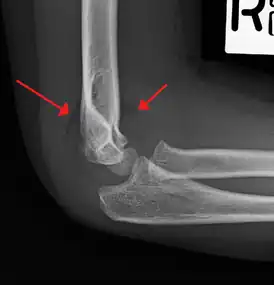

| An elbow X-ray showing a displaced supracondylar fracture in a young child | |

A supracondylar humerus fracture is a fracture of the distal humerus just above the elbow joint. The fracture is usually transverse or oblique and above the medial and lateral condyles and epicondyles. This fracture pattern is relatively rare in adults, but is the most common type of elbow fracture in children.[1] In children, many of these fractures are non-displaced and can be treated with casting. Some are angulated or displaced and are best treated with surgery. In children, most of these fractures can be treated effectively with expectation for full recovery.[2] Some of these injuries can be complicated by poor healing or by associated blood vessel or nerve injuries with serious complications.

A supracondylar humerus facture is diagnosed by x-ray and the injured limb will be examined to assess the surrounding soft tissue, neurovascular status, and to identify any other injuries to the affected area.[5] Pain, swelling, and deformity near the elbow or arm area is common and a bleed near the fracture may result in an effusion in the elbow joint. With severe displacement, there may be an anterior dimple from the proximal bone end trapped within the biceps muscle. The skin is usually intact. If there is a laceration that communicates with the fracture site, it is an open fracture, which increases infection risk. For fractures with significant displacement, the bone end can be trapped within the biceps muscle with resulting tension producing an indentation to the skin, which is called a "pucker sign".

Fat pad sign/sail sign - A non-displaced fracture can be difficult to identify and a fracture line may not be visible on the X-rays. However, the presence of a joint effusion is helpful in identifying a non-displaced fracture. Bleeding from the fracture expands the joint capsule and is visualized on the lateral view as a darker area anteriorly and posteriorly, and is known as the sail sign.[8]